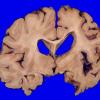

NEURODEGENERATION

Corticobasal Degeneration (CBD) (8)